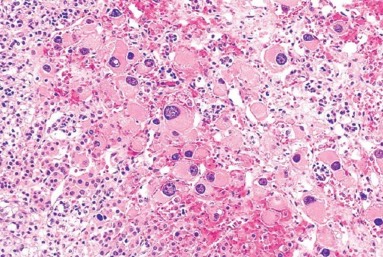

1096. В коре надпочечников мертворожденного мальчика были обнаружены очень крупные клетки. эти изменения могут быть связаны с